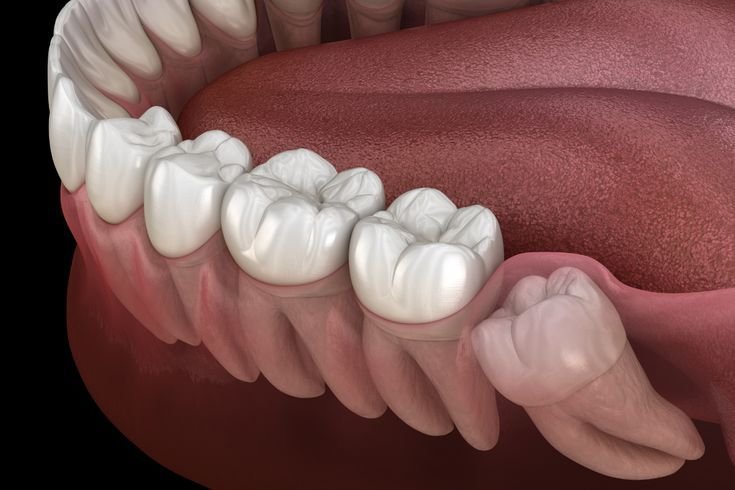

Are you struggling with discomfort and swelling due to wisdom teeth home remedies? Whether you’re in your teens or noticing issues even at wisdom teeth age 40, wisdom teeth can cause pain, irritation, and difficulty chewing. According to recent dental research, nearly 85% of adults experience some form of wisdom tooth complication, making natural remedies a safe and effective alternative to medication. Studies show that targeted home treatments can reduce inflammation, soothe gums, and even prevent infections without the side effects of over-the-counter painkillers.

In this blog, we’ll explore 7 natural wisdom teeth home remedies you can trust. By the end, you’ll gain actionable, research-backed strategies to relieve pain, improve oral hygiene, and understand more about the role of your wisdom teeth—like their potential wisdom teeth benefits and how many you should have. This guide is designed for beginners and advanced readers alike, making it easy to implement these remedies safely at home.

Understanding wisdom teeth home remedies can make the often-painful process of eruption or impaction much easier. By incorporating these natural strategies, you can reduce pain, control swelling, and even prevent infections. Whether you’re dealing with delayed eruptions, multiple wisdom teeth numbers, or simply want to maximize the wisdom teeth benefits, these remedies offer safe, research-backed solutions for everyone.

Remember, while home remedies are effective, regular dental checkups are essential, especially if you notice prolonged pain, swelling, or other complications. With these natural remedies, comfort and oral health are always within reach!